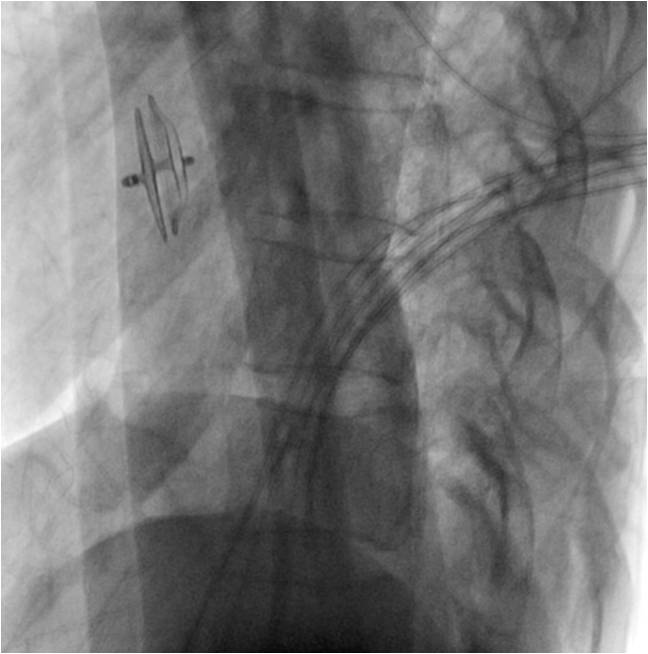

明确诊断后,荆志成带领先心病微创手术团队为患者实施了卵圆孔未闭封堵术。经大腿根部的股静脉微创置入心脏导管将封堵器送到卵圆孔位置后,展开封堵伞,与卵圆孔完美契合,封堵住缺口。李女士术后第二天恢复良好,顺利出院。

卵圆孔未闭封堵术中,采用封堵伞堵住缺口(图片由北京协和医院提供)